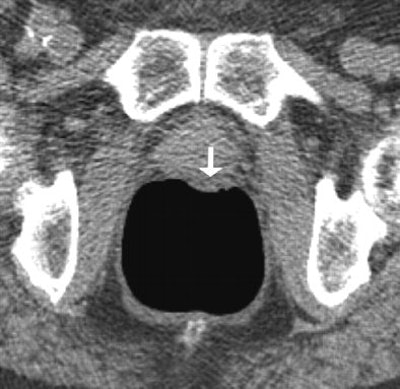

| Above: Supine image of rectum in a 64-year-old woman shows nontagged material 6 mm or greater with small hyperdense spot in dependent part of rectum (arrow). Hyperdense spot probably corresponds to some barium. Below: Prone view of rectum in the same patient shows nontagged fecal material has moved to anterior rectal wall (arrow). Image shows nontagged feces 6 mm or larger in rectum, possibly caused by remnants of bisacodyl suppository. P Lefere, S Gryspeerdt, J Marrannes, M Baekelandt, B Van Holsbeeck, "CT Colonography After Fecal Tagging with a Reduced Cathartic Cleansing and a Reduced Volume of Barium" (AJR 2005, 184: 1836-1842). |

Overall the researchers found residual feces in 413 segments (34.41%), including fecal material smaller than 6 mm in 210 segments (17.5%) and 6 mm or larger in 203 segments (16.92%). In addition, 527 segments contained residual fluid (43.91%), detected as it moved between prone and supine imaging. Nontagged feces 6 mm or greater were present in 49 segments (4.08%) and nontagged fluid in 178 segments (14.83%).

"The false positives were caused in four patients because of diverticulosis with severe luminal narrowing and thickening of the folds," Lefere and colleagues commented. In these cases, a differential diagnosis that included carcinoma was made. Only 4% of segments presented with untagged feces 6 mm or larger, and this result was limited to the presence of one fecal ball in more than two-thirds of these patients.